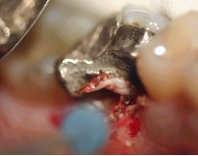

In one single treatment, the gingivectomy can done and the tooth stump is prepared.